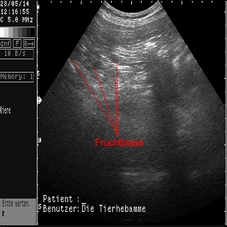

Das sind die ersten Ultraschallbilder vom 28.05.2014!

Es hat wirklich geklappt!

Die Tier-Hebamme hat 9 kleine Fruchtblasen gezählt...!!!

In den ersten Tagen änderte sich nichts an Mayas Verhalten, das wir nicht auch schon von Scheinschwangerschaften kannten. Deswegen waren wir wahnsinnig auf den ersten Besuch der Tier-Hebamme gespannt, die uns am 28.05.2014 endlich besuchte, um einen Ultraschall zu machen!

Wir haben die lange Wartezeit kaum ausgehalten und dann doch irgendwie geschafft! Mit einem positiven Ergenis, wie man an den Bildern sehen kann. Sage und schreibe neun kleine Fruchtblasen waren für das (geübte) Auge der Hebamme zu erkennen - wir haben nix gesehen....  Uns dafür aber unglaublich gefreut!!!!